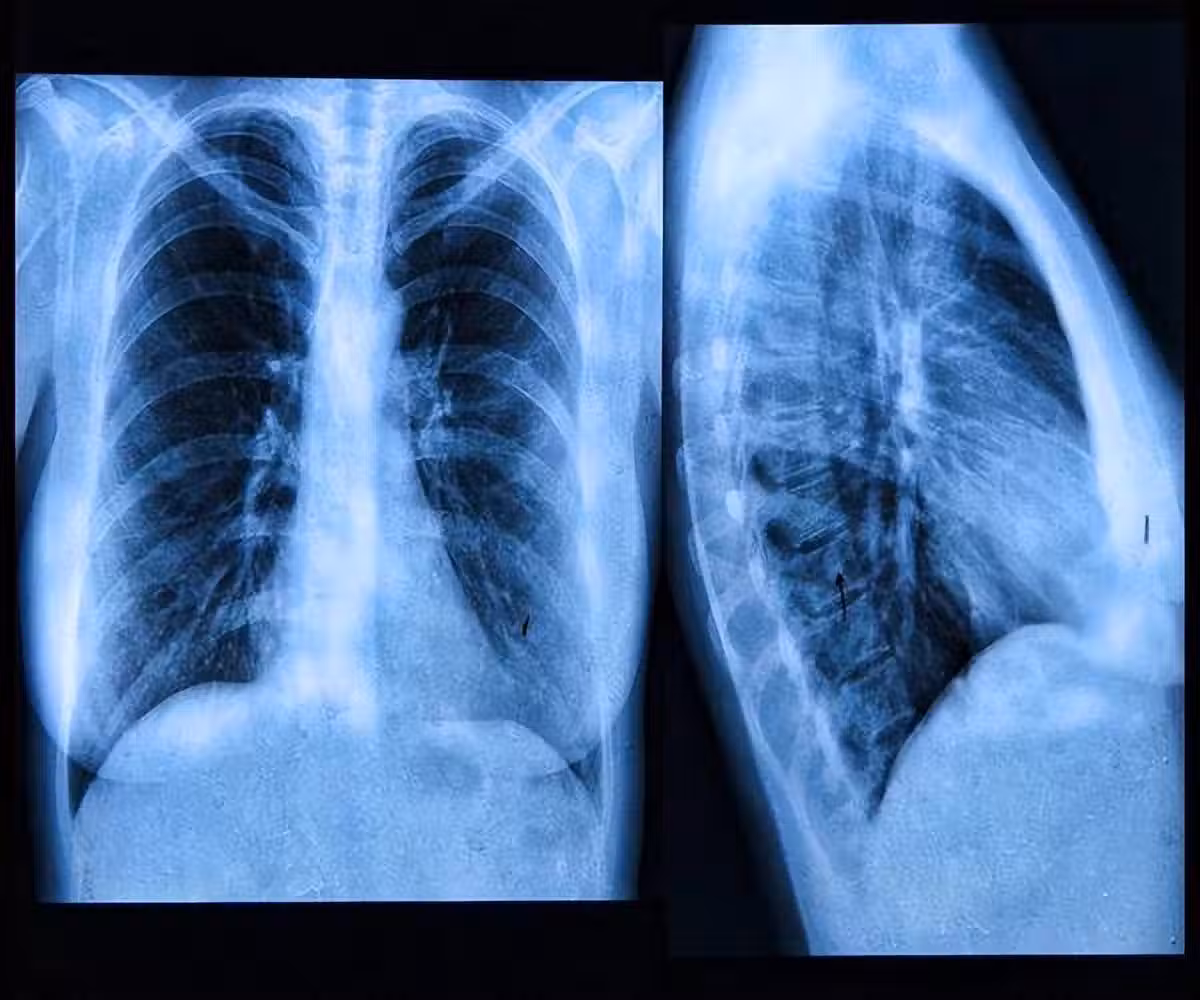

肺內有癌,腿疼告知?事實上,早期肺癌的5個跡象你更需要去關注

4、肺部持續疼痛

如果人的肺部持續疼痛,也有可能是肺癌造成的,隨著病情的發展,肺癌也會引起骨骼疼痛和肌肉疼痛。

這種痛感多發生在背部和肩部,運動程度越大,疼痛感也會有所增加。因此患上肺癌是禁止做任何劇烈運動的。